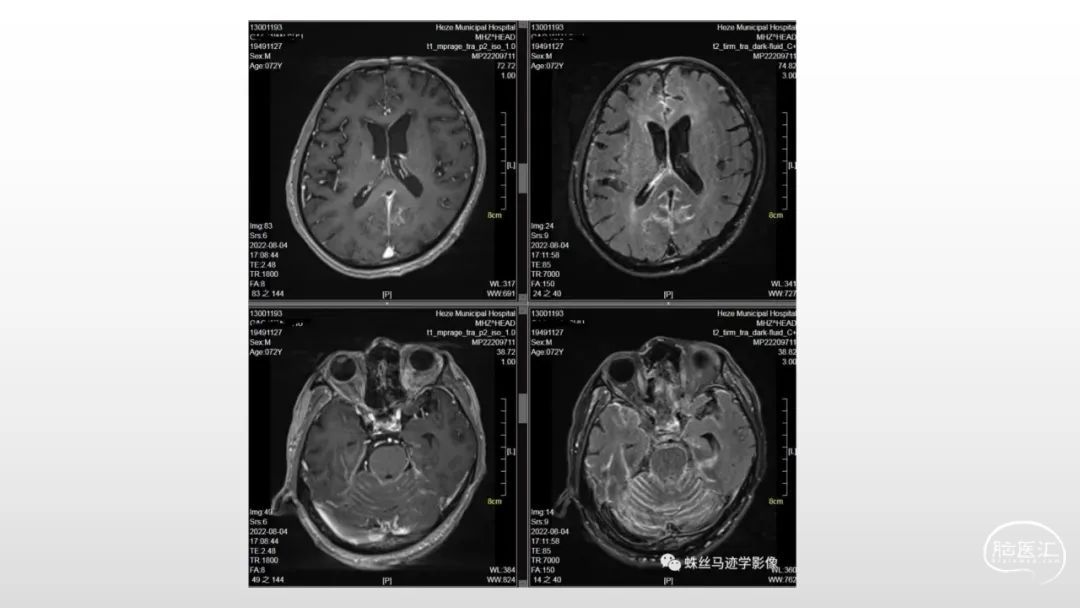

颅脑影像诊断基础知识讲座:脑膜病变

菏泽市立医院